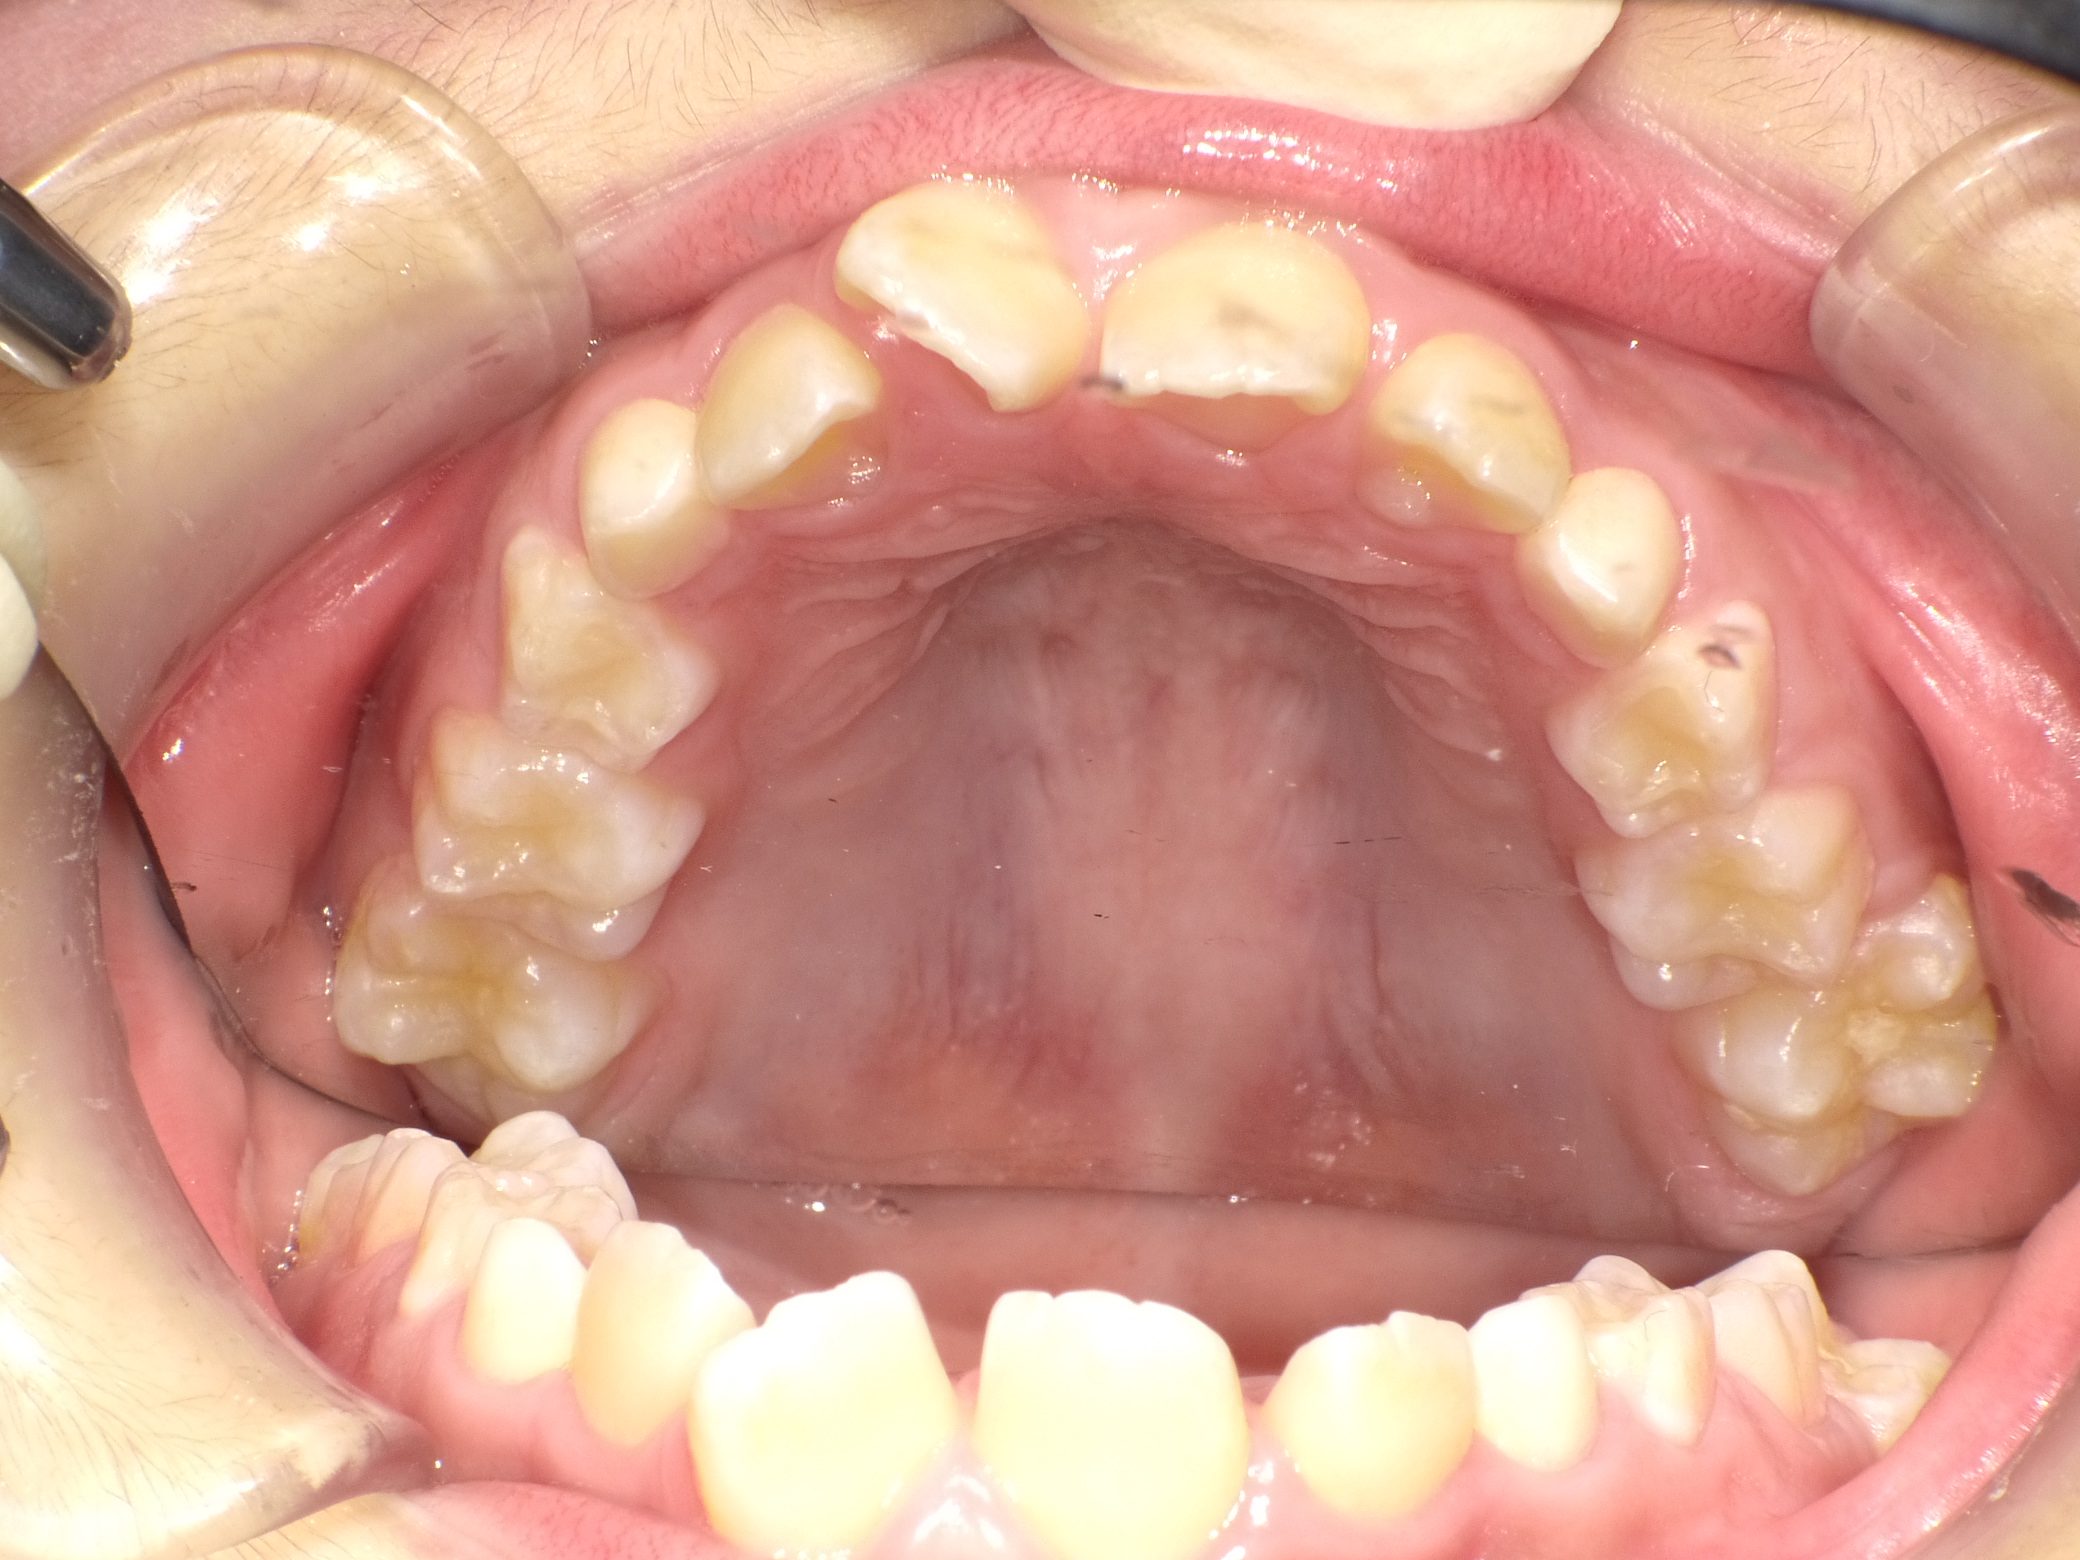

【小学生】マイオブレース矯正 上顎前突(出っ歯)と叢生(でこぼこ)を改善

小学生で開始

マイオブレース

でこぼこ

出っ歯

過蓋咬合

非抜歯

1期治療のみで改善

Before

After

治療期間

2.1年

治療開始

8歳

種類

マイオブレース矯正

使用装置

機能矯正装置

コメント

咬み合わせのズレを改善するために 矯正をされました

しっかり取り組んでくれてスムーズに終了しました